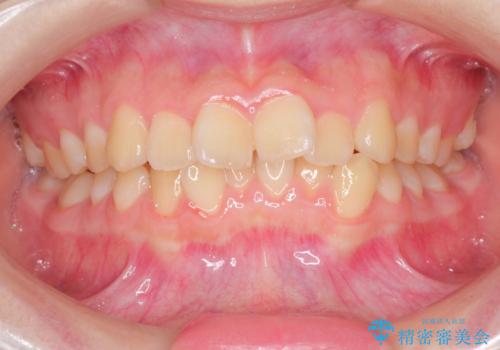

なるべく通院回数を減らして矯正したい インビザラインでのガタガタ矯正

- 上下の歯並びを治したいとのことで来院されました。

受験生ということもあり、なるべく通院回数を減らしての矯正を希望されたので、インビザラインで治療をすることにしました。